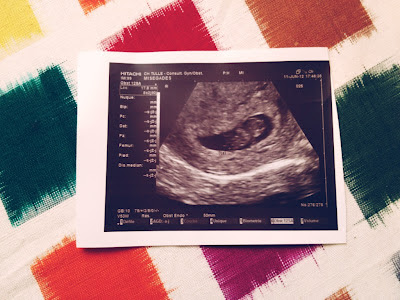

We went straight to the sonogram and I held my breath while Logan squeezed my hand really hard.  Sure enough, up popped a BEAUTIFUL little blob! It looked nothing like our previous sonograms from the miscarriage- there was no mistake that this was a BABY... we were able to see its head and body, it wiggled its little nubs, and the doctor asked us the very thing that we were dying to hear... "Would you like to hear the heartbeat?" We said YES! It was music to my ears.  I burst into the happiest, most emotional, sobbing tears.  The doctor was a bit confused/ concerned with my reaction and I clarified "I am just SO HAPPY!" He then went on to say this was a very EARLY, STRONG, HEARTBEAT... word for word what we had prayed since Day 1 in the car with Morgan.  It was then that he said we had his blessing for me to go to Dallas and things were looking great and on track at 8 weeks! This was also the appointment where we got our January 28th due date and the affirmation that I needed in order to announce the pregnancy to my family and close friends while I was in Dallas.

Our little blob at 8 weeks.  Little head on the right and body/ nubs on the left.